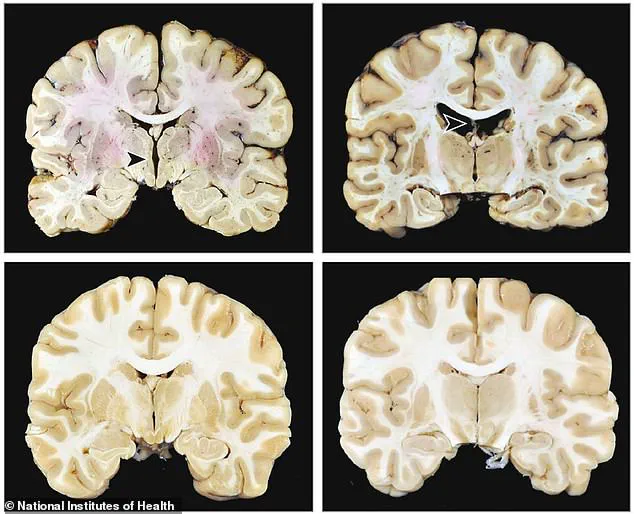

Chronic traumatic encephalopathy (CTE), a neurodegenerative disease linked to repeated head trauma, is primarily diagnosed through post-mortem brain examinations.

Researchers identify the condition by examining the buildup of tau protein in specific brain regions, including the frontal lobe.

This area is critical for functions such as problem-solving, self-control, emotion regulation, impulsivity, and aggressive behavior.

The accumulation of tau in these regions is a hallmark of CTE and is often associated with significant behavioral and cognitive changes in affected individuals.

Brain imaging and post-mortem studies have revealed significant structural changes in athletes diagnosed with CTE.

These include enlarged ventricles, which indicate brain shrinkage; holes in brain tissue; thinning of key areas; and clogged blood vessels.

Such damage is a direct result of repeated head trauma and underscores the physical toll of contact sports on the brain.